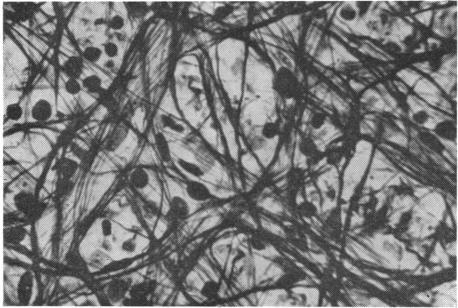

RETINAL PATHOLOGY AFTER CENTRAL RETINAL VEIN OCCLUSION.

Br J Ophthalmol. 1961 Oct;45(10):683-94. doi: 10.1136/bjo.45.10.683.